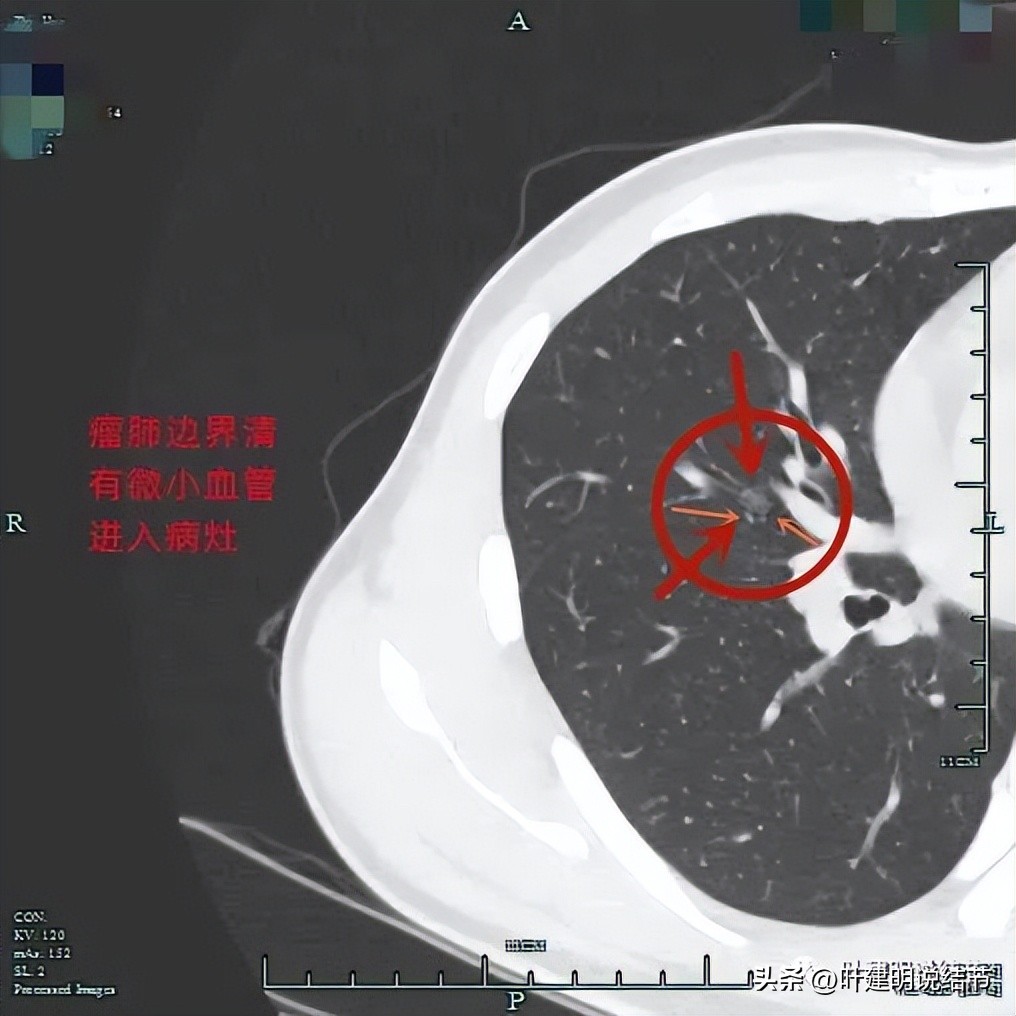

再来看靶扫描影像:

病灶1:

右肺中叶多发结节,主病灶与次病灶均为磨玻璃密度,主病灶瘤肺边界清,轮廓也很清,并有血管进入,总体实性成分不明显,但因明显的血管征,考虑应该至少微浸润性腺癌可能性大,也不能完全除外浸润性腺癌的贴壁型,可以考虑手术治疗;次病灶位于近肺门部,也是磨玻璃结节,而且边不光整,密度也显各不均匀,怀疑原位癌或微浸润性腺癌可能性大。虽然目前小而没有实性成分,但如果主病灶要干预,此灶也得一并切除;病灶三由于非常微小,而且密度甚高,虽有空泡征,仍考虑是良性的可能性大得多(空泡征或空腔征在实性结节中不适用作为恶性特征表现之一)。